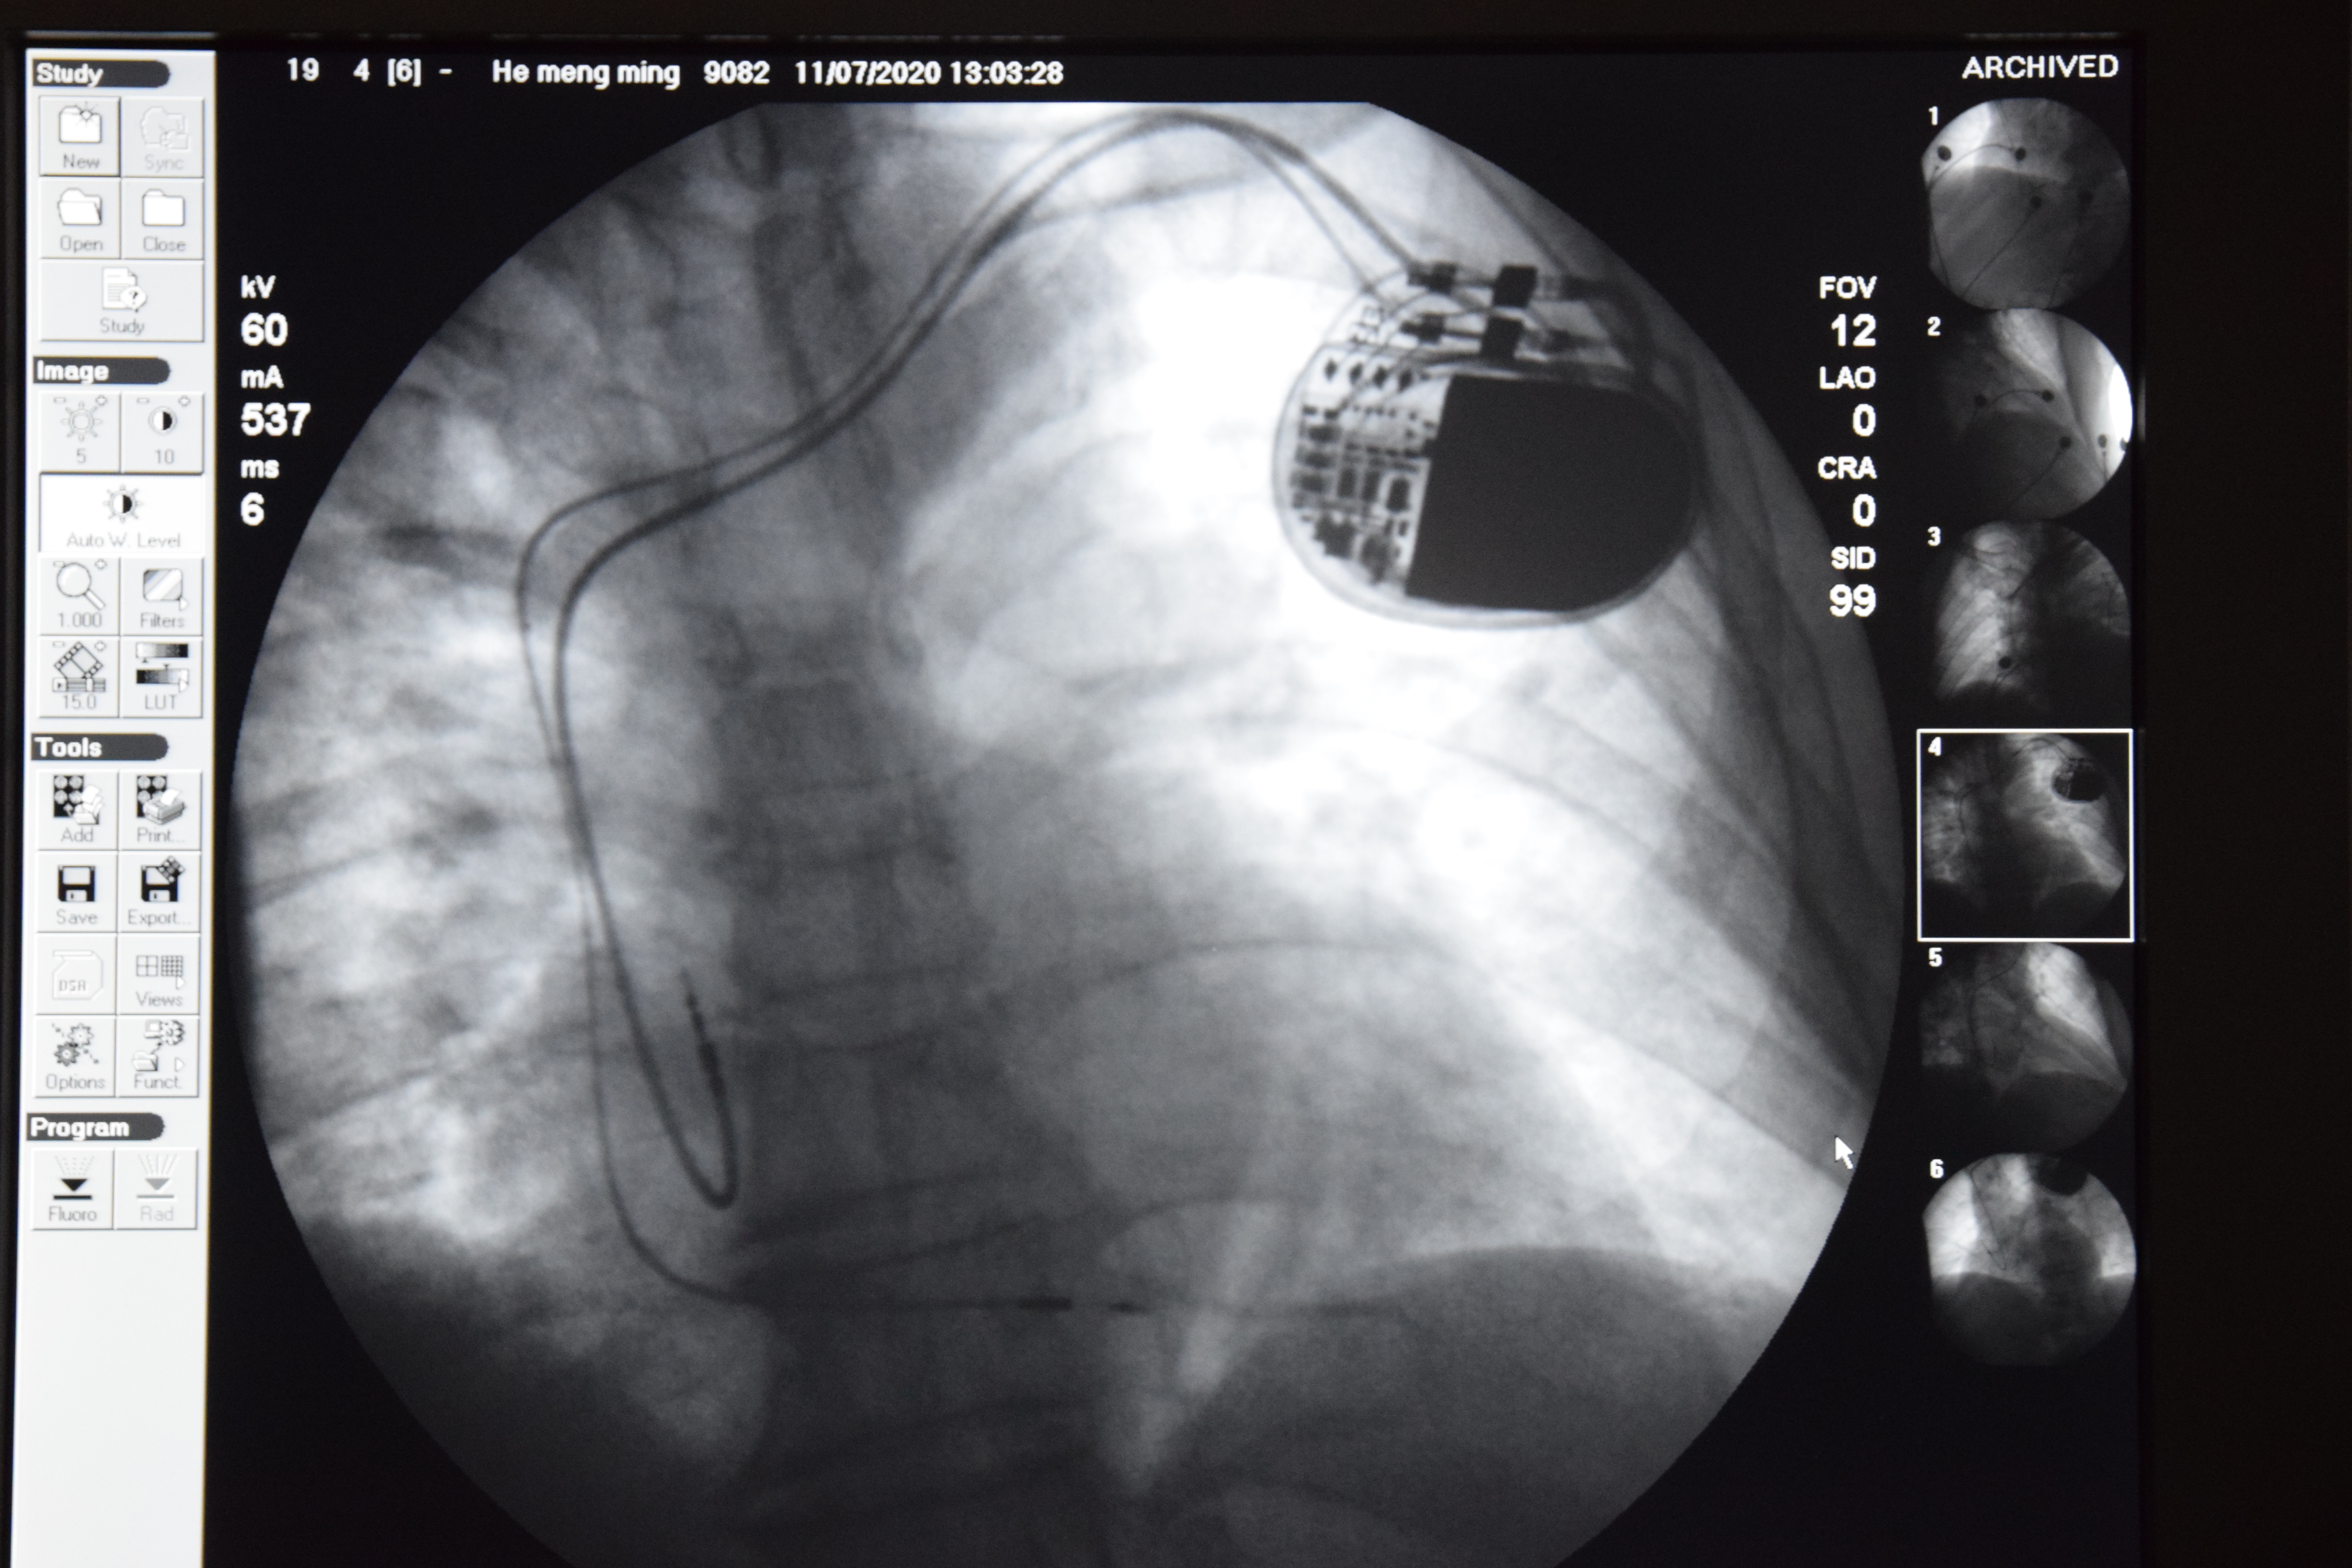

图为希浦系统起搏术中影像

希浦系统起搏是目前备受关注的生理性起搏,该手术效果好、损伤小,能够减轻患者的医疗费用负担。其难点在于将起搏器电极准确植入希氏束或左束支区域,与自身房室传导相同或相似,不仅是心脏跳动,还保留了心脏正常的收缩顺序,在最大限度保护患者心功能的同时,达到生理性起搏的目的。此次心血管内科介入手术团队成功为患者实施希浦系统起搏手术,将心室电极植入左束支区域起搏,术后,患者心电图基本达到正常的QRS间期,其症状消失,达到了预期治疗效果。